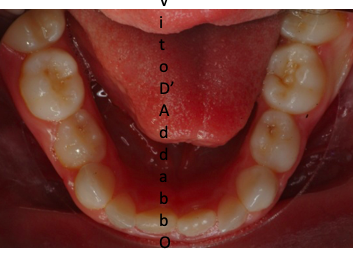

prima